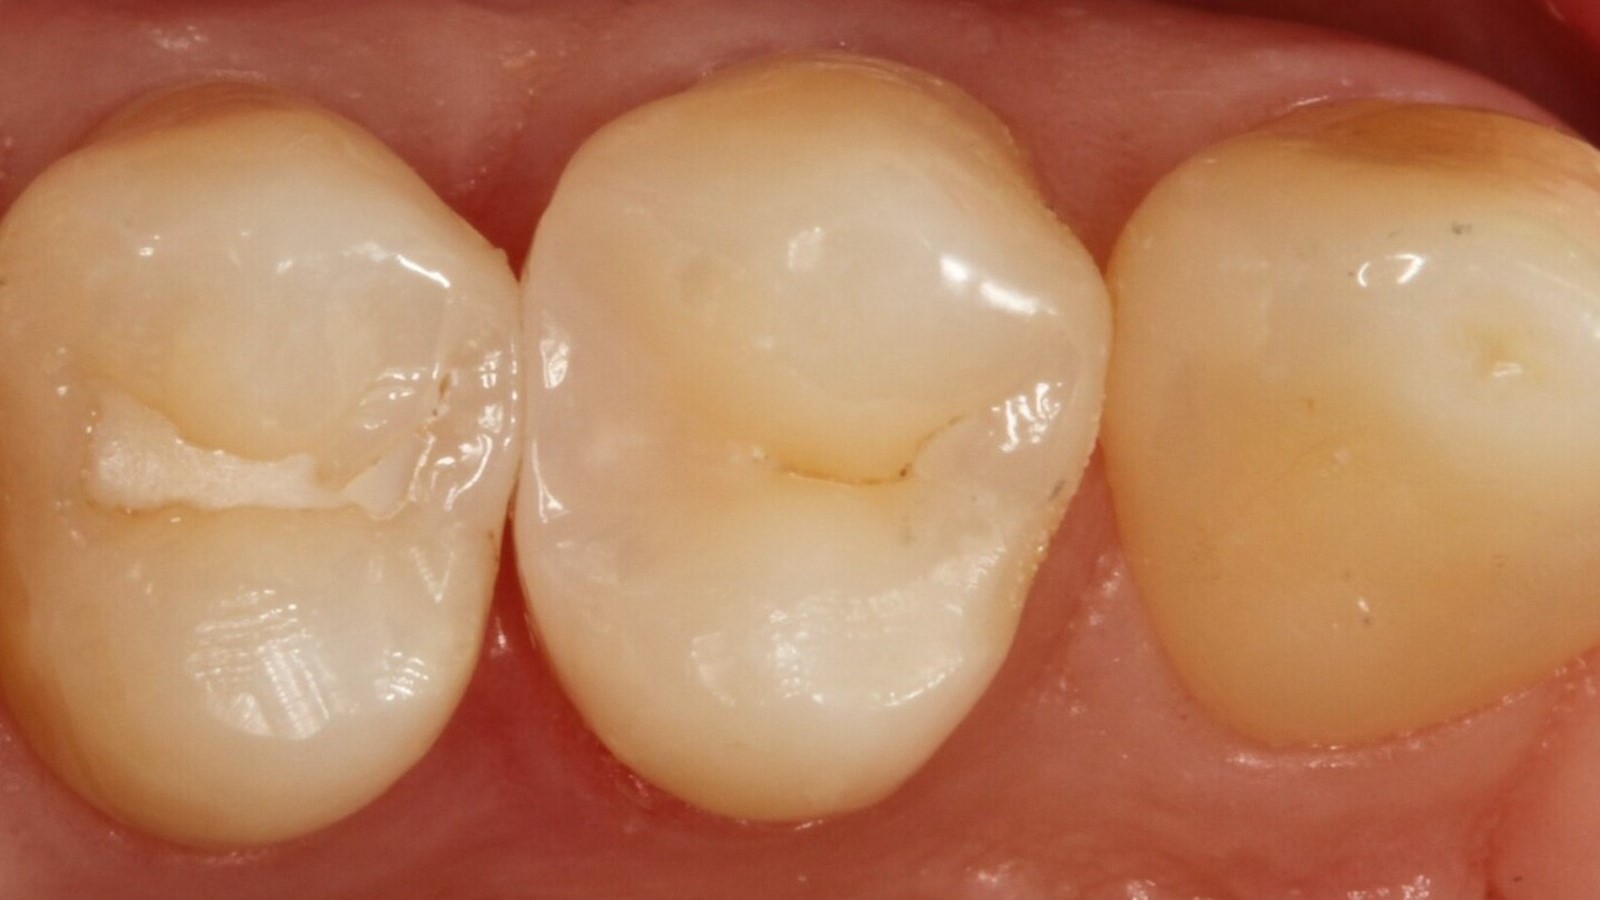

Professor Ernst first identified the hidden caries and opened the carious lesion to show the patient the problem (Fig. 1-2). He then excavated the caries, prepared the cavity and placed a sectional matrix (Fig. 3) before sealing the cavity with adhesive (Fig. 4). In a single step, he filled the cavity with Venus Bulk Flow ONE (Fig. 5). Once the restoration was completed, Prof. Ernst polished it (Fig. 6) and took a control radiograph, which also shows the excellent radiopacity of Venus Bulk Flow ONE (Fig. 7).